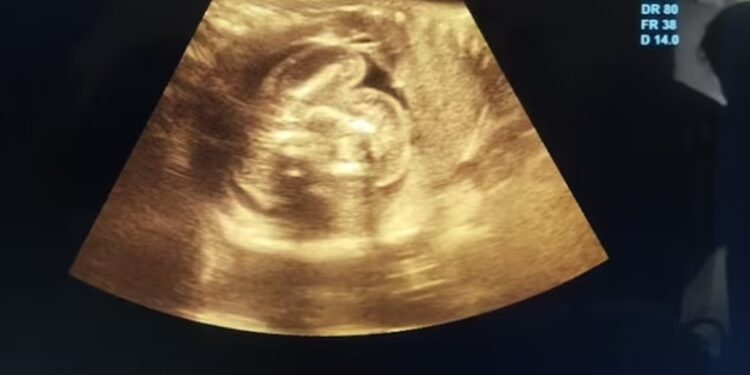

Σπάνιο ιατρικό περιστατικό: Δύο έμβρυα βρέθηκαν στο στομάχι αγέννητου μωρού

Ένα σπάνιο ιατρικό φαινόμενο συνέβη σε μία γυναίκα στην Ινδία, όταν ανακαλύφθηκε ότι το αγέννητο μωρό της είχε δύο άλλα αναπτυσσόμενα έμβρυα μέσα στο σώμα του. Η 32χρονη επισκέφθηκε το νοσοκομείο για έναν υπέρηχο ρουτίνας, ενώ ήταν έγκυος 35 εβδομάδων.

Αν και οι προηγούμενοι υπέρηχοί της ήταν φυσιολογικοί, οι γιατροί εντόπισαν «μία επιπλέον δομή που περιείχε οστά» στην κοιλιά του αγέννητου αγοριού της. Στη συνέχεια, η περαιτέρω εξέταση αποκάλυψε δύο εμβρυϊκές μορφές μέσα στην κοιλιά του μωρού.

Το φαινόμενο, που ονομάζεται «έμβρυο εντός εμβρύου» (Fetus in Fetu/FIF), είναι εξαιρετικά σπάνιο και έχει καταγραφεί μόλις 200 φορές στη ιατρική βιβλιογραφία, αναφέρει η Daily Mail, με εκτιμώμενη συχνότητα 1 στις 500.000 γεννήσεις.

Δεν είναι σαφές πόσες από αυτές τις 200 περιπτώσεις περιλάμβαναν πολλαπλά έμβρυα. Η γυναίκα γέννησε το μωρό της στις 1 Φεβρουαρίου, ενώ ήταν περίπου 35 εβδομάδων, και οι γιατροί αφαίρεσαν τα δύο έμβρυα από το στομάχι του μωρού, τα οποία είχαν σταματήσει να αναπτύσσονται σε κάποιο σημείο της εγκυμοσύνης.